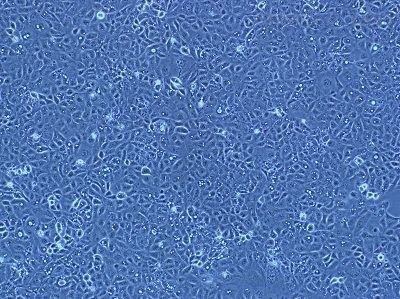

Tca-8113

- 生长状态:

贴壁生长

Tca-8113(舌鳞癌细胞)全程提供细胞生物体、生长特性、来源、器官、类型、形态、培养条件、应用、组织、冻存条件等复苏及冻存细胞株说明书信息,专业的技术支持您的细胞系实验,让您实验再无烦扰!培养的前一周内出现质量问题,客户可凭细胞的照片以及书面形式的细胞培养,实验操作过程提供给我司。经技术人员核实认定为可以予以重发的情况,由我司再免费提供一次细胞。